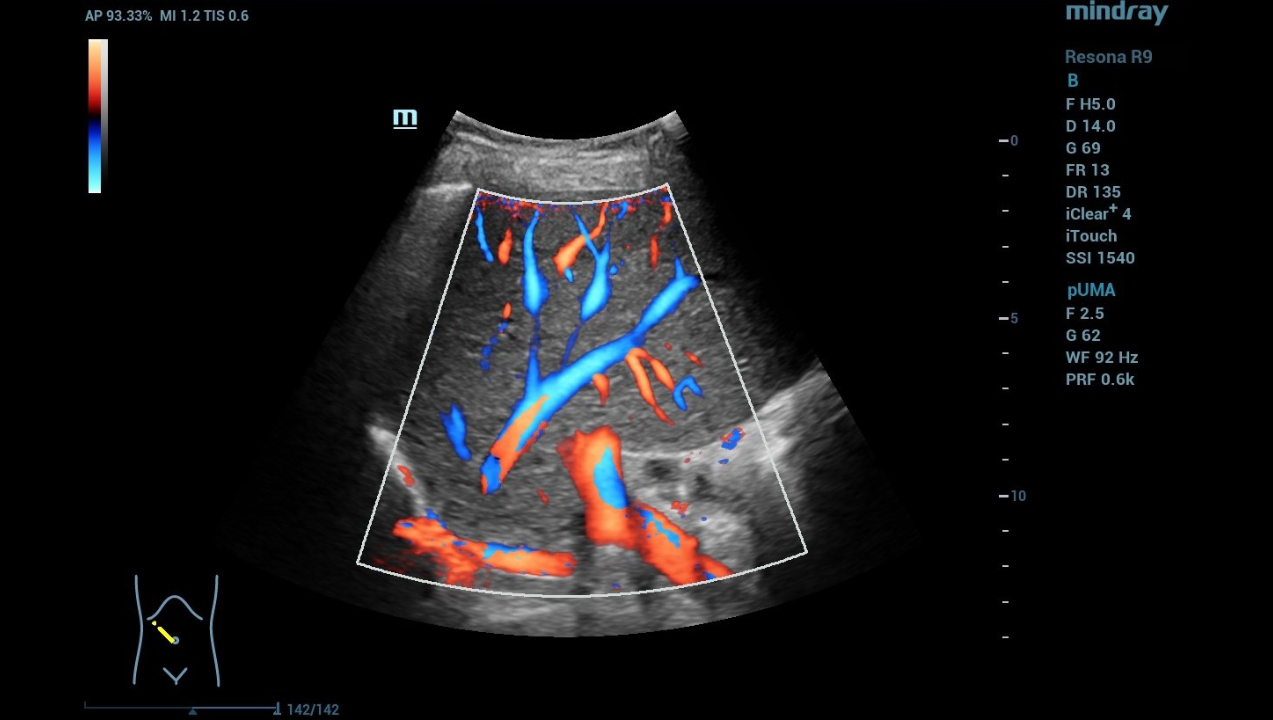

Jung: The first tumor signs are that the vessels in the surrounding area are changing. UMA ensures that I can also beam the probe from any angle also vertically and assess the morphology of the liver.

In locating the foci, the Ultra Micro Angiography (UMA) function of the system assisted us, because UMA makes it possible to assess the vascular situation of the liver independently of the angle and without artifacts.

hifr-ceus-liver-fig5-pc

Ultra Micro Angiography (UMA)